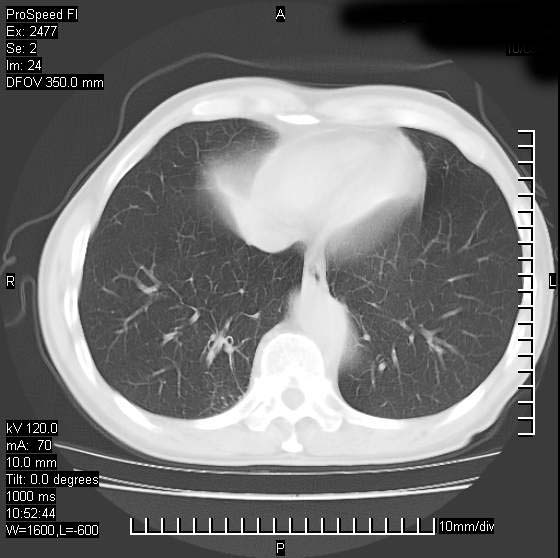

以下是引用天南地北在2007-10-9 14:29:00的发言:[br]1:右上肺结核[br]2:右肺下叶肿块:不支持肺癌,首先考虑炎性病变-肺脓疡可能性大[br]理由:1:临床病史支持,肺脓肿症状不明显应该是不规则服药造成。[br] 2:肿块边缘模糊,周围可见炎性渗出,长毛刺,内见支气管征,不过有点不规则。[br] 我感觉下肺癌这个诊断有点偏左,建议积极抗炎治疗后复查

以下是引用卜一在2007-10-9 15:55:00的发言:[br][br] [br] 1:右上肺结核[br]2:右肺下叶肿块:不支持肺癌,首先考虑炎性病变-肺脓疡可能性大[br]理由:1:临床病史支持,肺脓肿症状不明显应该是不规则服药造成。[br] 2:肿块边缘模糊,周围可见炎性渗出,长毛刺,内见空气支气管征,不过有点不规则。[br] 我感觉下肺癌这个诊断有点偏左,建议积极抗炎治疗后复查![br]支持! [br] [br] [br]

以下是引用wxy7406在2007-10-9 21:02:00的发言:[br]结合临床病史首先考虑感染性病变,但周围型肺癌不能除外,1.患者年龄偏大2.临床有咯血3.(也觉得是最重要的一点)病灶内有偏心性空洞。

以下是引用王仕学在2007-10-9 13:48:00的发言:[br]右下肺周围性肺癌可能性大,最好活检吧

以下是引用hhcckk在2007-10-9 15:18:00的发言:[br]右上肺病灶考虑结核,病灶多种形态并存(纤维化、增殖性病灶并存)[br]右下肺病灶比较难说,个人意见更趋向于“天南地北”的诊断----肺脓肿[br]1、病人有明显的寒战,高热,肿瘤病人很少出现[br]2、病灶周围的肺纹理走向柔和,没有肿瘤病灶常见的集束征[br]3、病灶边缘的毛刺较长,恶性肿瘤多为短毛刺[br]痰中血丝和病人的年龄是两个不利于良性肿块的因素,建议早点活检

以下是引用ydx_74在2007-10-9 15:53:00的发言:[br]右上肺结核,右下中心性肺癌可能大,肺门淋巴结肿大。